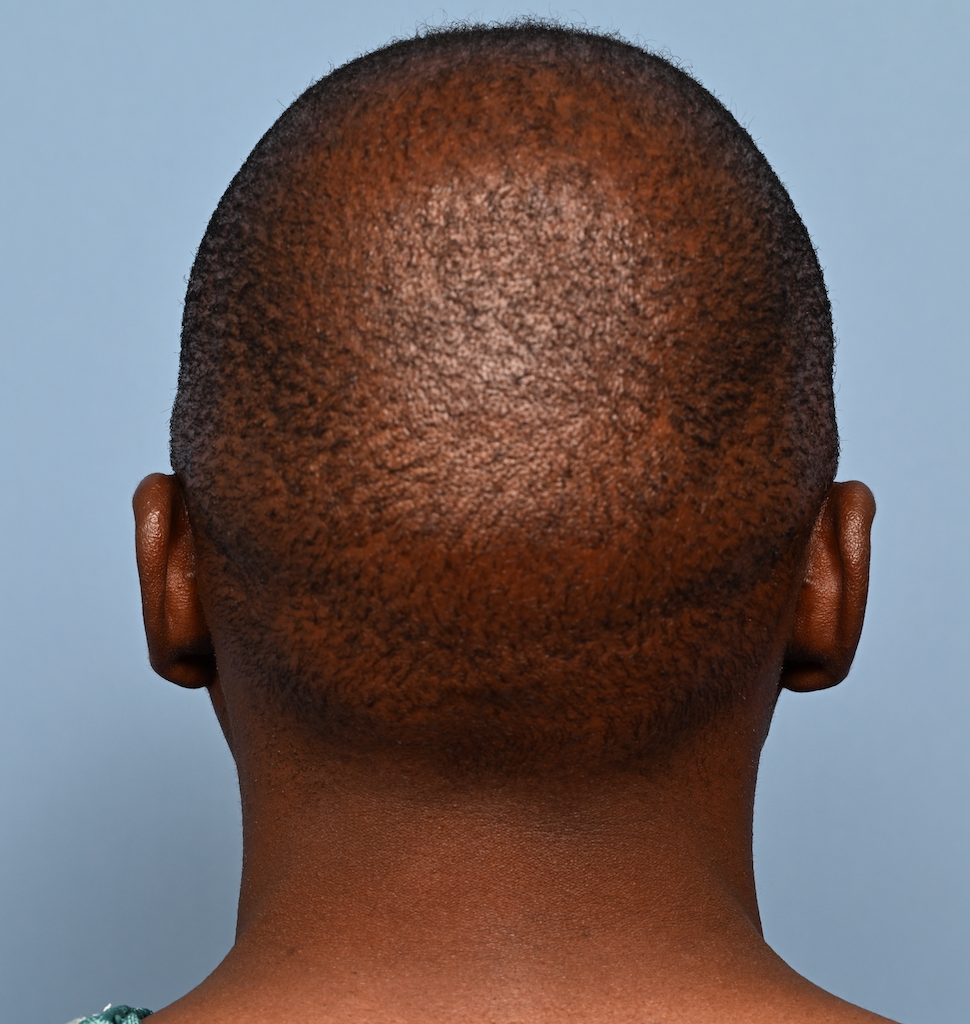

Desire for reshaping of an asymmetric flat back of the head in a shaved head male.

A combined back of the head reshaping procedure was done with a custom skull implant, sagittal ridge reduction and a right temporal muscle reduction.

Desire for reshaping of an asymmetric flat back of the head in a shaved head male.

A combined back of the head reshaping procedure was done with a custom skull implant, sagittal ridge reduction and a right temporal muscle reduction.